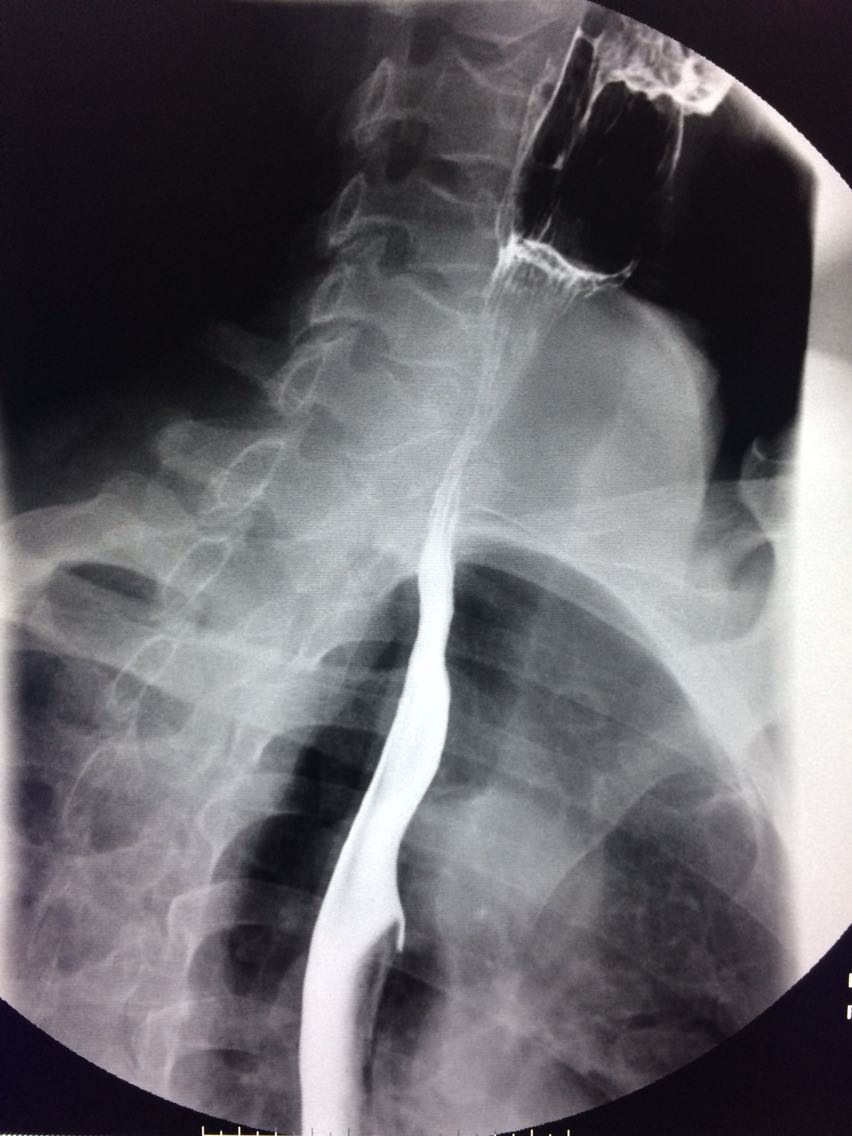

一例溃疡型胃癌。

男,45岁 反复胃疼5年余。 5年来,反复出现胃疼,进食后半小时加重,经常感觉饥饿,当地按胃溃疡,给予阿莫西林,奥美拉唑治疗,具体不详,效果欠佳,遂入院,入院来,饮食睡眠,二便可。 既往体健。 入院上消化道造影如图。

如图

讨论,诊断及鉴别诊断? 胃溃疡的影像表现? 溃疡良恶性的鉴别? 入院后行胃大部切除术。 诊断,胃腺癌。